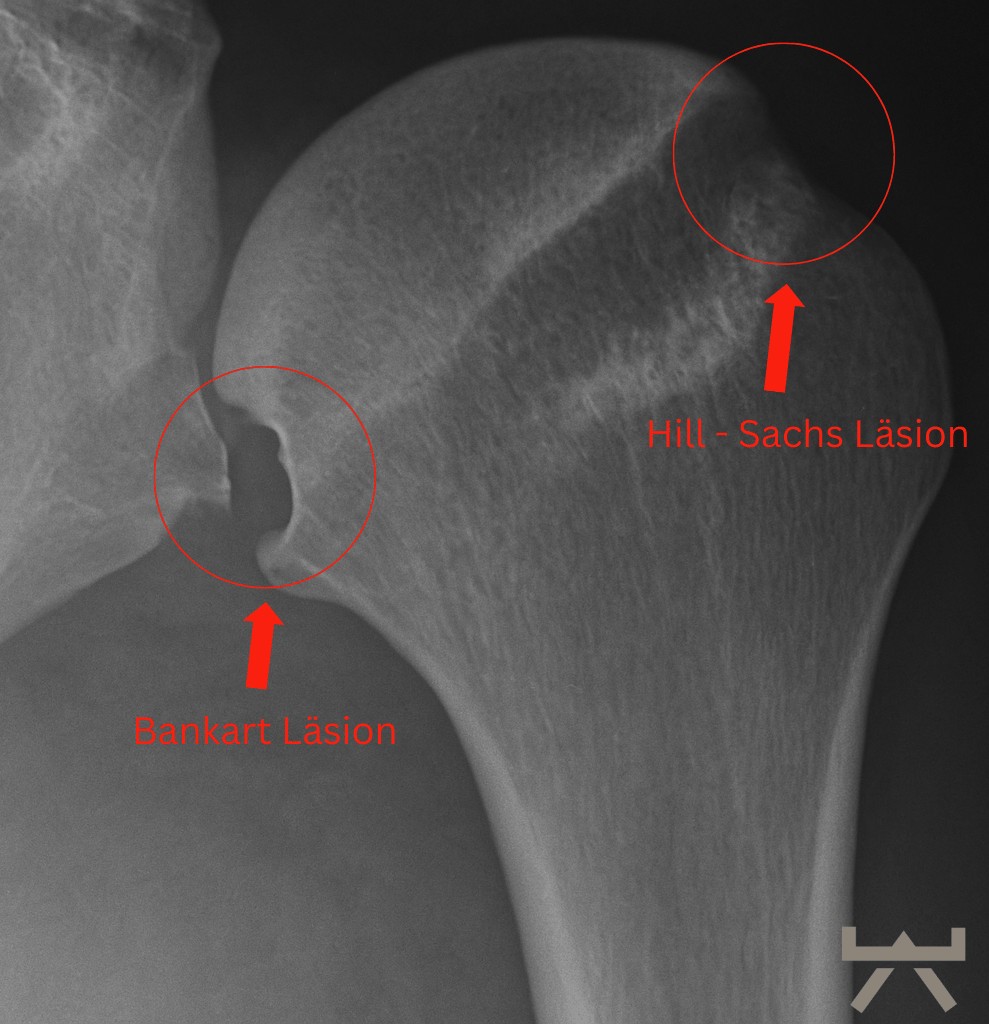

In einigen Fällen können bei einer traumatischen Schulterluxation mehrere Strukturen beschädigt werden. Zunächst kann einmal das Bindegewebe der Kapsel und/oder des Labrums gedehnt werden oder reißen. Zum anderen kann sich eine knöcherne „Bankart-Läsion“ entwickeln, bei der es durch den Aufprall zu einer Fraktur am unteren Ende der Schulterpfanne kommt. Dies geht häufig mit einer „Hill-Sachs-Läsion“ einher, einer Delle in der Schulterkopf selbst. Eine Röntgenaufnahme der Schulter kann dies entweder zeigen oder ausschließen.

Bei einer (traumatischen) Auskuglung ist es wichtig, dass eine Bildgebende Untersuchung durchgeführt wird, um weitere Läsionen und mögliche Brüche auszuschließen.